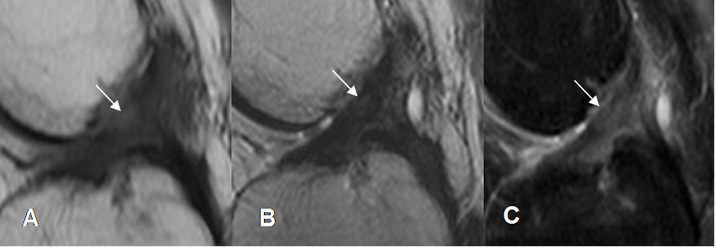

Fig 107. Ruptura parcial del LCA.

A: RM sagital en T1, B: RM sagital en T2 y C: RM sagital en STIR. Pérdida del patrón fibrilar, con ruptura de algunas fibras en el tercio medio del LCA (Flechas), por ruptura parcial.